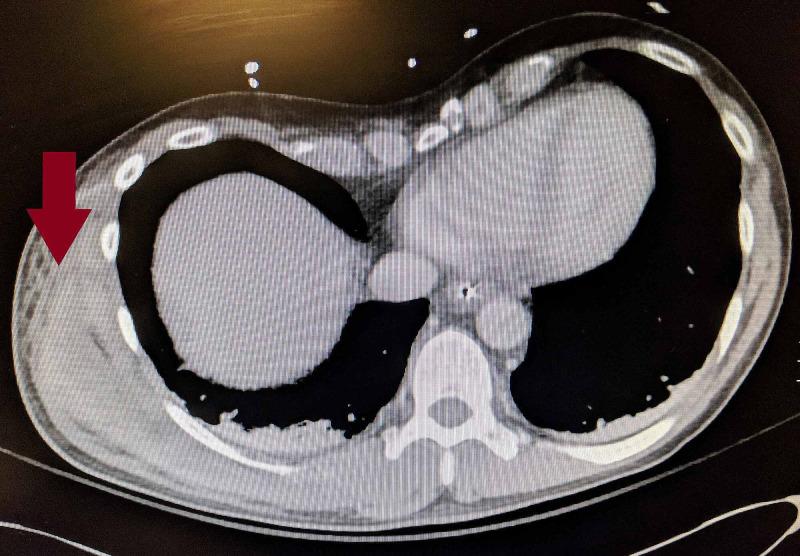

Necrotizing soft tissue infections typically begin with direct inoculation of bacteria into the subcutaneous tissues. Here, we present a case with no such exposure, but with severe necrotizing fasciitis. We present a middle-aged man presented to the emergency department for a presumed allergic reaction after having initially sought care twice at an urgent care facility. The patient had swelling, but no tenderness of his right lateral chest and flank. Subsequent imaging showed extensive fluid in the fascial planes of the right chest wall requiring surgical debridement. Necrotizing fasciitis that is not treated with surgical debridement carries a mortality rate approaching 100%. This case highlights a potential atypical presentation as well as highlights the fact that the Laboratory Risk Indicator for Necrotizing Fasciitis (LRINEC) score lacks sensitivity to rule out a necrotizing soft tissue infection, requiring surgical debridement for diagnosis.

摘要

坏死性软组织感染通常始于细菌直接接种到皮下组织。在此,我们报告一例没有此类暴露史,但患有严重坏死性筋膜炎的病例。我们介绍一名中年男性,他最初在紧急护理机构就诊两次后,因疑似过敏反应而被送往急诊科。患者右侧胸壁和侧腹肿胀,但无压痛。随后的影像学检查显示右胸壁筋膜平面有大量积液,需要手术清创。未经手术清创治疗的坏死性筋膜炎死亡率接近100%。该病例突出了一种潜在的非典型表现,同时也突出了坏死性筋膜炎实验室风险指标(LRINEC)评分在排除坏死性软组织感染方面缺乏敏感性这一事实,需要手术清创来进行诊断。